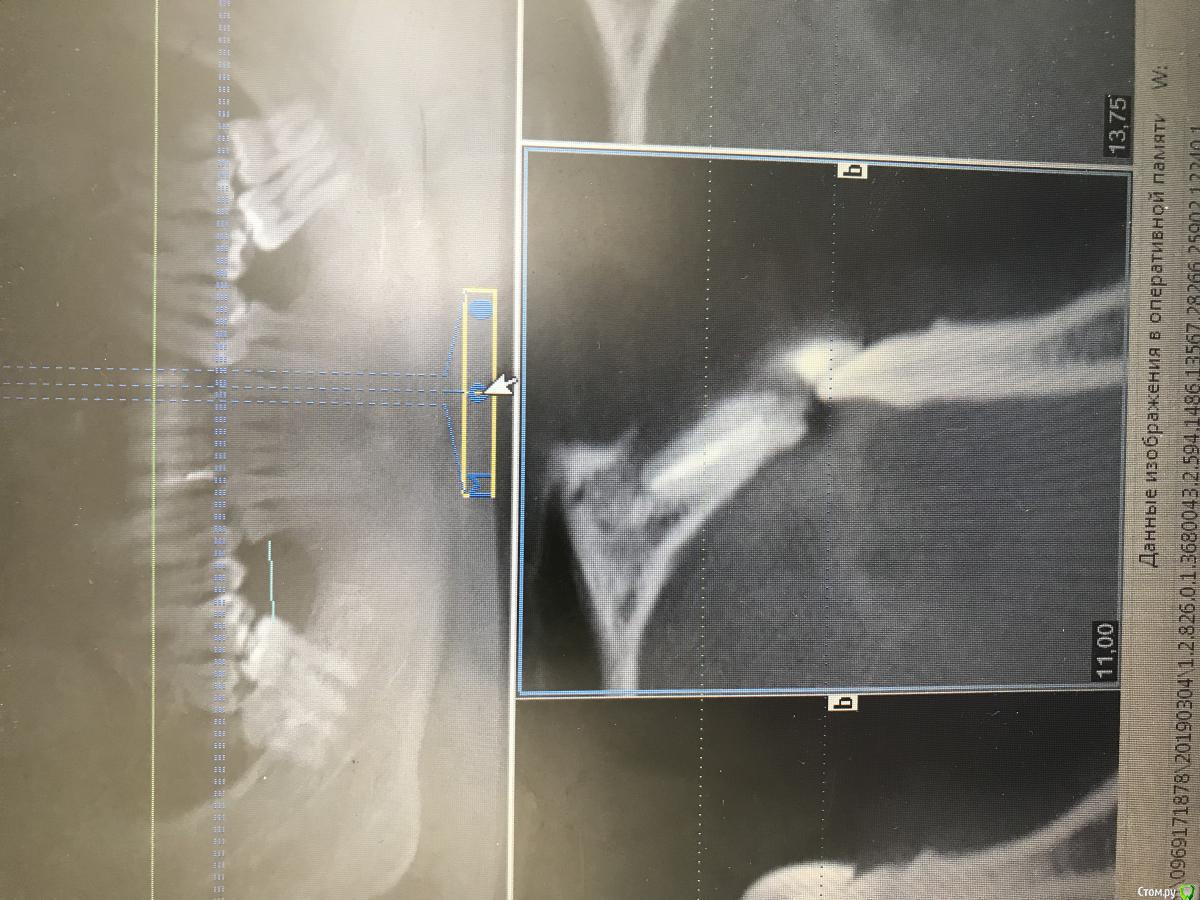

dr.Dre Опубликовано 20 марта, 2019 Поделиться Опубликовано 20 марта, 2019 (изменено) Добрый день коллеги.Сделал НКР с нерезорбируемой мембраной permamem с вестибулярки зафиксировал пином ,небно просто завернул,пациент сегодня пришёл на осмотр, мембрана оголилась ,десна сместилась небно ,после операции прошло 5 дней,гигиена хорошая, как вы ведёте такие ситуации?Читал в книге Иштвана Урбана что данное осложнение бывает ,нужно выждать 6 недель снять мембрану, и зафиксировать коллагеновою и мобилизировать лоскут . Изменено 20 марта, 2019 пользователем dr.Dre Ссылка на комментарий

dr.Dre Опубликовано 20 марта, 2019 Автор Поделиться Опубликовано 20 марта, 2019 А по какому поводу нкр, и в какой области? Я бы вел под метрогилом и ополаскивателями. Что-то не помню что б урбан одну коллагеновую на другую менял, там скорее всего про птфе речь шла.Метрогил назначил,нкр в области 22,мембрана птфе permamem Ссылка на комментарий

dr.Dre Опубликовано 20 марта, 2019 Автор Поделиться Опубликовано 20 марта, 2019 Опишите протокол операции. Одномоментно с удалением была НКР?Нкр была одномоментно с удалением.1.Удалил корень ,очистил лунку от грануляций2.Скелетировал слизистую3.Адаптировал мембрану так чтоб не касалась зубов.4.Фиксировал пином, вестибулярно,внес костный материал cerabon,мембрану завернул язычно,мобилизировал лоскут , наложил швы . Ссылка на комментарий

kramer Опубликовано 26 марта, 2019 Поделиться Опубликовано 26 марта, 2019 У вас мембрана зубов касается... 2 Ссылка на комментарий

dr.Dre Опубликовано 26 марта, 2019 Автор Поделиться Опубликовано 26 марта, 2019 У вас мембрана зубов касается...нет Ссылка на комментарий

Павел7809 Опубликовано 27 марта, 2019 Поделиться Опубликовано 27 марта, 2019 Мне кажется , что судя по снимку надо все разбирать... Ссылка на комментарий

dr.Dre Опубликовано 27 марта, 2019 Автор Поделиться Опубликовано 27 марта, 2019 Мне кажется , что судя по снимку надо все разбирать...почему? Ссылка на комментарий

syrovovec Опубликовано 29 марта, 2019 Поделиться Опубликовано 29 марта, 2019 Фото не самые удачные, но я за все убрать, пока хуже не стало, вроде и небно рецессия....расстояние между корнями маленькое, и если мембрана и не касается, то очень близко. Ссылка на комментарий